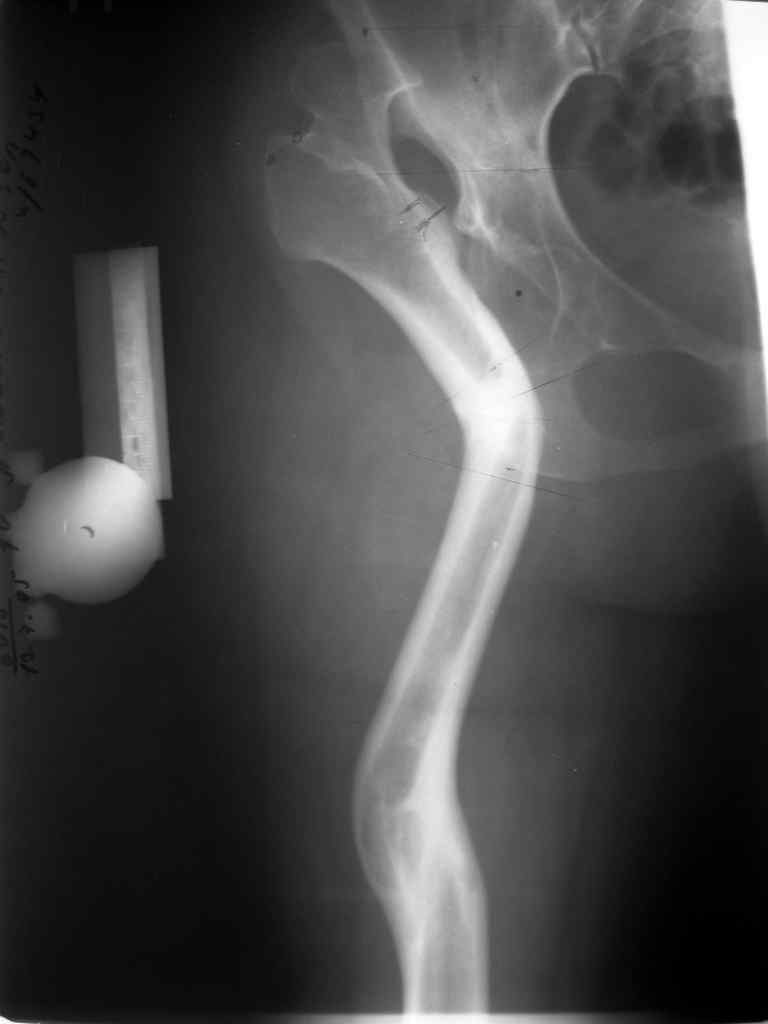

Moghno i tak kak sdelali my: pelvic support + tibial and equinus correction .

Слайд 1

Слайд 2

Слайд 3

Слайд 4

Devushka predstavlennaya na snimke nachala s LLD 9 cm, valgus deformation of the tibia, huge Trendelenburg( vidno na snimke).

Seichas : no LLD ,no Trendelenburg, reasonable hip motion.A samoe glavnoe ei ne predstoit kaghdye 10-15 let delat revision THR.